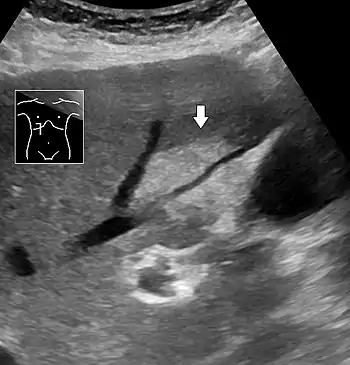

Liver steatosis (fatty liver disease) as seen on CT

On X-ray computed tomography (CT), the increased fat component will decrease the density of the liver tissue, making the image less bright. Typically the density of the spleen and liver are roughly equivalent. In steatosis, there is a difference between the density and brightness of the two organs, with the liver appearing darker.[12] On ultrasound, fat is more echogenic (capable of reflecting sound waves). The combination of liver steatosis being dark on CT and bright on ultrasound is sometimes known as the flip flop sign.

On abdominal ultrasonography, steatosis is seen as a hyperechoic liver as compared to the normal kidney.